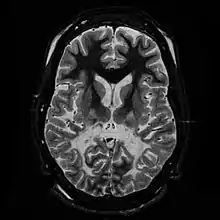

| White matter, with reduced volume and increased signal intensity. The anterior white matter is spared. Features are consistent with X-linked adrenoleukodystrophy. | |

The Loes score is a rating of the severity of abnormalities in the brain found on MRI. It ranges from 0 to 34, based on a point system derived from the location and extent of disease and the presence of atrophy in the brain, either localized to specific points or generally throughout the brain. A Loes score of 0.5 or less is classified as normal, while a Loes score of 14 or greater is considered severe. It was developed by neuroradiologist Daniel J. Loes MD and is an important tool in assessing disease progression and the effectiveness of therapy.[13]